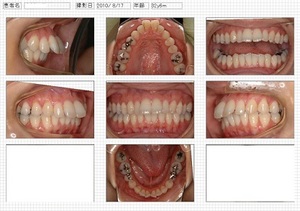

終了時写真

治療期間:2年01ヶ月

治療総費用:852000円(税込)

上顎前突治療例(30代 女性)

主訴 ①出っ歯、②横顔を鏡で見たとき口元が出ている

分析 歯の前方傾斜が標準値より大きい、口唇が標準値より突出している

治療方針 歯の傾斜と横顔、そしてズレを改善するために抜歯治療を選択

治療前

治療後

横顔

治療前

治療後

治療期間:2年01ヶ月

治療総費用:852000円(税込)

歯の傾斜を改善することで下顎も良い位置へ。

矯正治療により横顔も改善することができました。

歯を並べるだけでなく、「 Face is first (顔が大切)」も大切だと思います。

両方達成することは簡単ではありませんが患者さんとともに追求していきたいです。